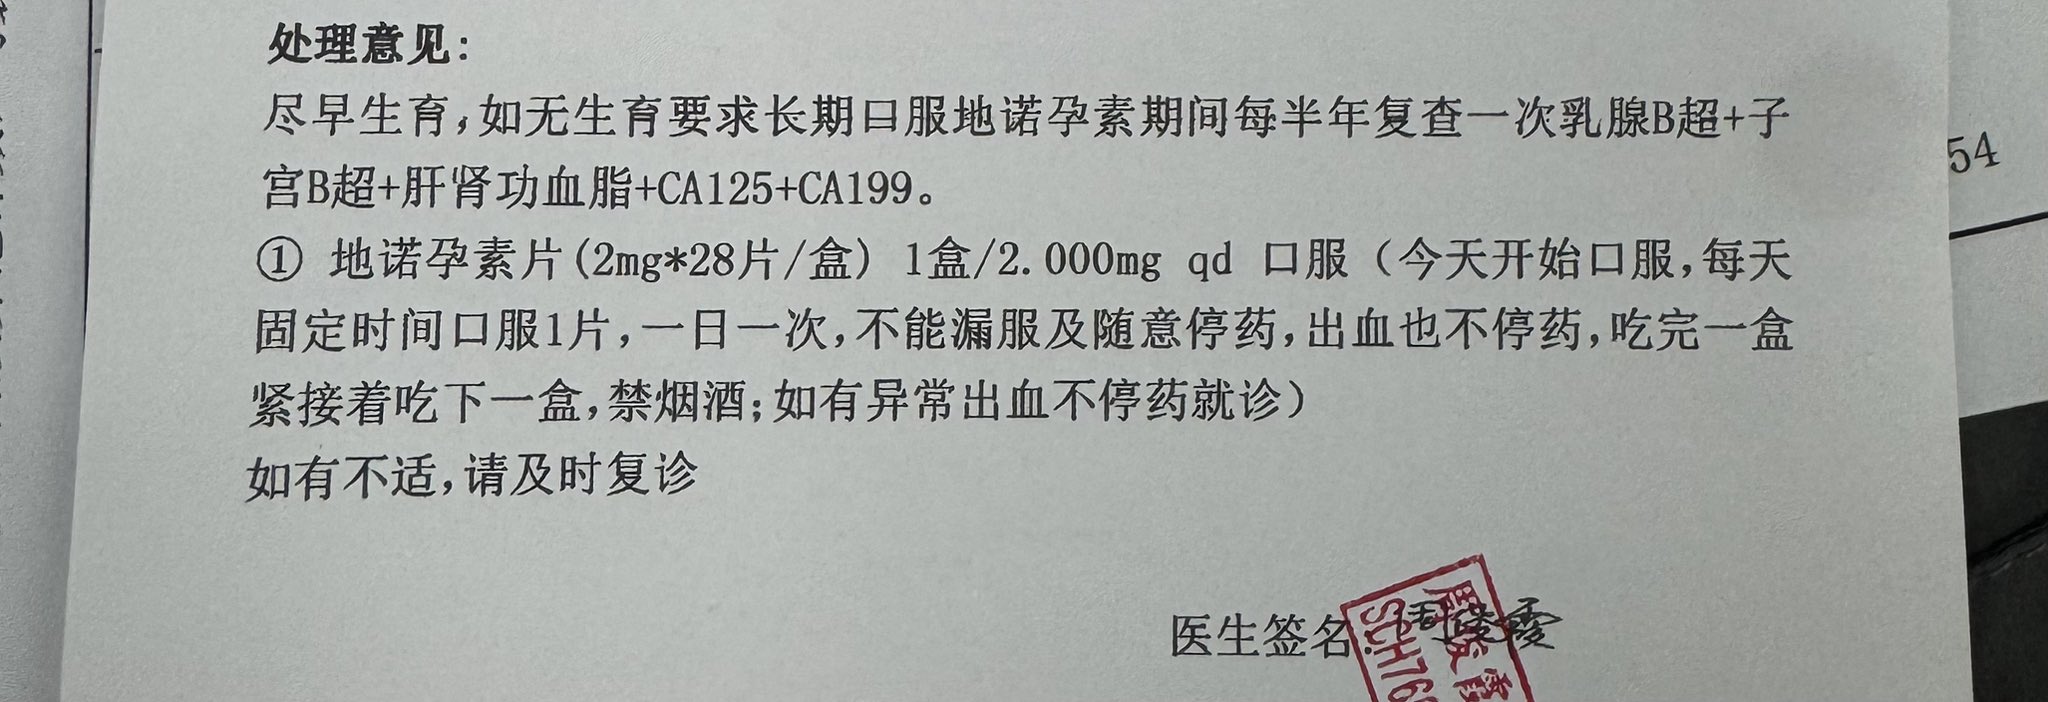

由于我现在快(痛经)痛死了,有感而发简单说说止痛药

常见NSAIDs先稍稍,首选塞来昔布,0.5-1h起效,对肠胃刺激小可以空腹服用,有中上的镇痛强度和中短的持续时间

那么有没有更强的呢🥹有,依托考昔,起效要1h以后,有着22h的长半衰期所以管一整天没什么问题,同样对胃刺激小适合我这种快痛晕过去了直接抓来吃

双氯芬酸钾起效也快适合空腹,但如果胃没那么好就可以一整个分不清哪里在痛了,所以还是垫点食物会比较好

那么再推荐一个双氯芬酸的直肠栓剂版本,直接绕过消化道刺激这关并且起效很快!